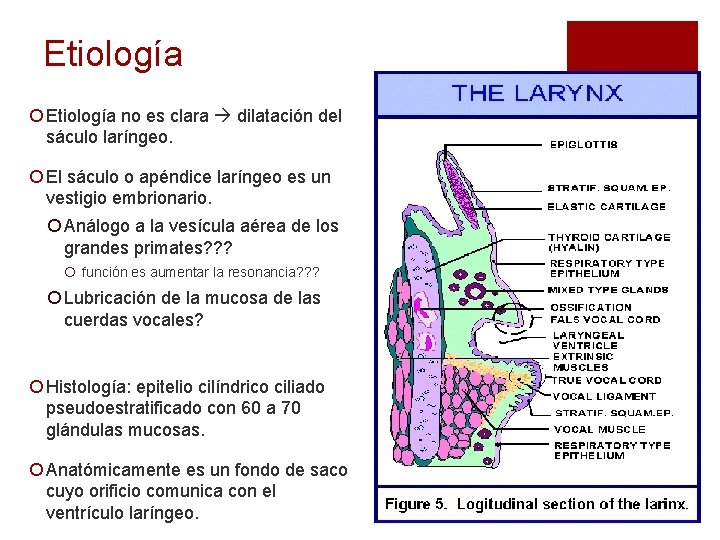

Etiología ¡ Etiología no es clara dilatación del sáculo laríngeo. ¡ El sáculo o apéndice laríngeo es un vestigio embrionario. ¡ Análogo a la vesícula aérea de los grandes primates? ? ? ¡ función es aumentar la resonancia? ? ? ¡ Lubricación de la mucosa de las cuerdas vocales? ¡ Histología: epitelio cilíndrico ciliado pseudoestratificado con 60 a 70 glándulas mucosas. ¡ Anatómicamente es un fondo de saco cuyo orificio comunica con el ventrículo laríngeo.